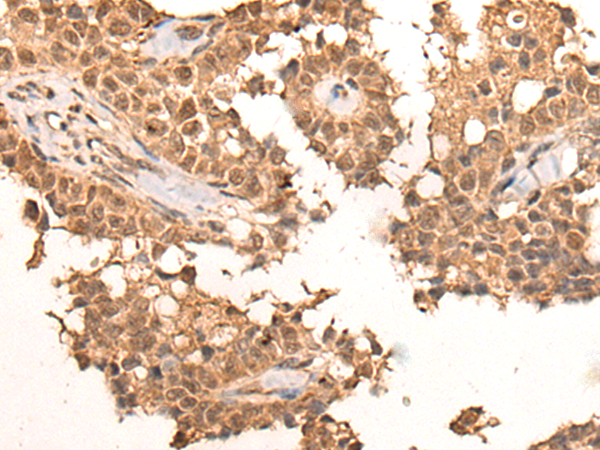

分类: 科研抗体货号: P04626别名:应用: IHC反应种属: Human, Mouse